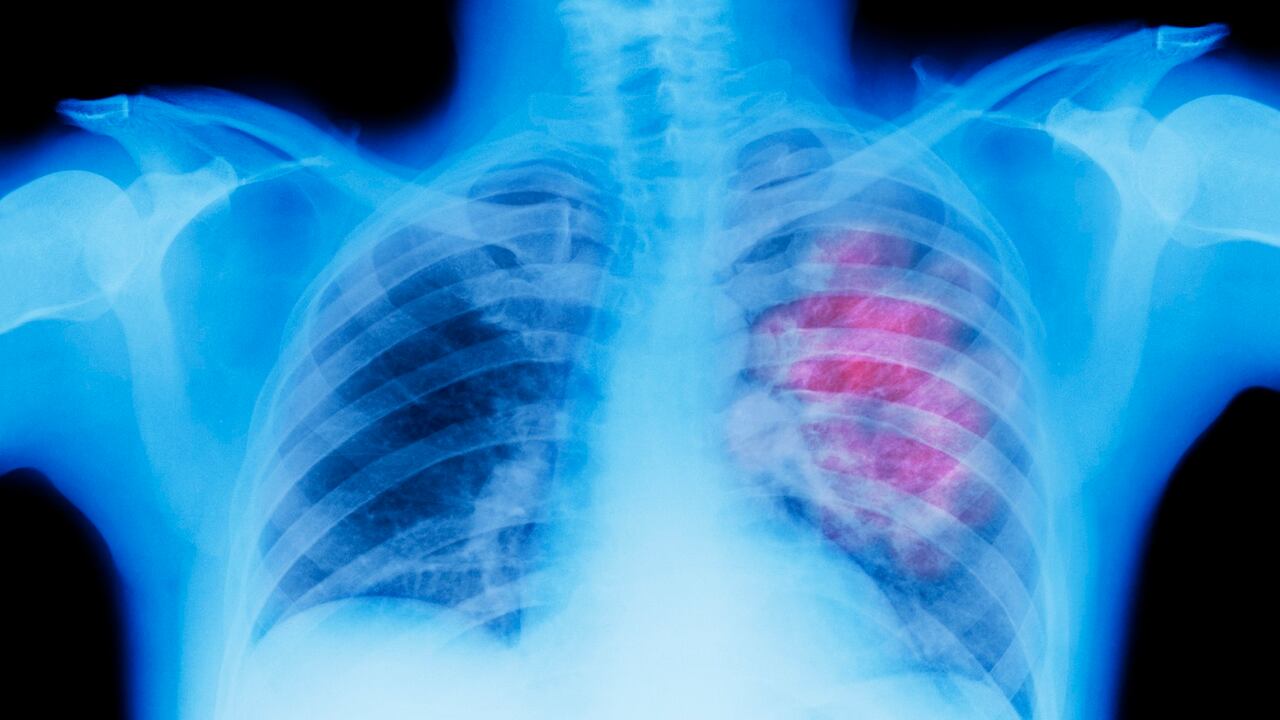

Cáncer de pulmón: ciencia descubre cómo aumentar la supervivencia un 20 % de uno de los cánceres con mayor mortalidad

En todo el mundo, un total de 2,206,771 personas fueron diagnosticadas con cáncer de pulmón en 2020, lo que lo convierte en el de más alta ocurrencia después del de mama. Y se estima que ese ha sido el promedio de enfermos en los años recientes, además de que se le considera uno de los cánceres más agresivos y letales que existen. Esta enfermedad afectó en el año 2020 a más de 6.876 personas en Colombia

Pero, una reciente investigación abre la esperanza para millones de pacientes. Fue publicada por la revista New England Journal of Medicine (NEJM), en cuyas páginas se socializó el estudio NADIM II del Grupo Español de Cáncer de Pulmón (GECP), que supone un cambio de paradigma al tratar con quimioterapia e inmunoterapia, antes de cirugía, a los tumores de pulmón intermedios, pero sin metástasis, lo que aumenta la supervivencia hasta en un 20 por ciento.